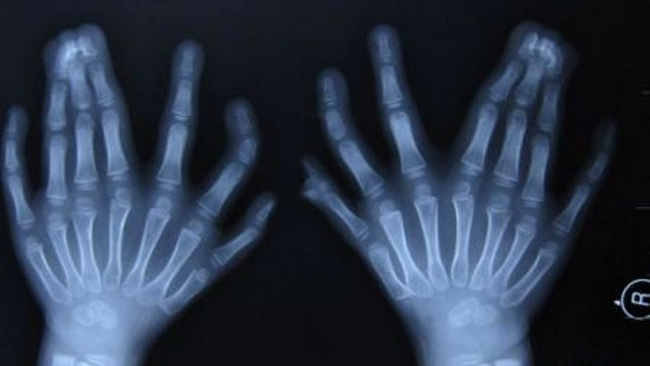

Baiatul cu 31 de degete este originar din Shenyang, China, si

probabil ca ar fi intrat in Cartea Recordurilor daca nu ar fi fost

operat ieri pentru a i se indeparta o parte din falange.

Chinezul are 15 degete la maini, dintre care 6 unite

(cate 3 la fiecare mana) si 16 degete la picioare.

Radiografia chinezului de 6 ani

Baiatul sufera de polidactilism, o boala care

se transmite genetic si duce la dezvoltarea mai multor degede decat

in mod normal.